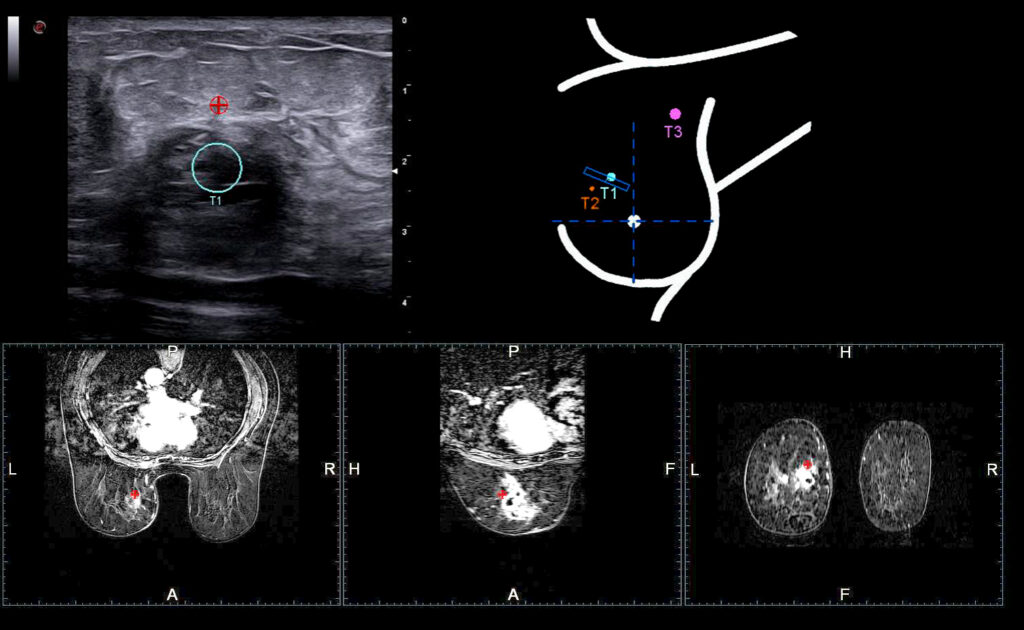

MyLab X90 er Esaote´s nye premiummodell og kommer i 2 spesialversjoner: MSK/Rauma og Brystdiagnostikk. Ultralydapparatet representerer et helt nytt kapittel og standard innen premium ultralyd.

Kliniske bilder.

SE3133 er en transvaginalprobe med frekevnsområde 9-3 Mhz for OB/GYN undersøkelser.